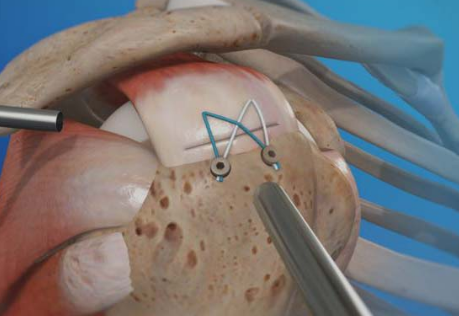

7. Como é a cirurgia?

A cirurgia é feita por artroscopia (mínima invasão). Passo a passo:-

- Limpeza do tecido doente]

- Preparação da área do osso

- Colocação de âncoras

- Sutura dos tendões rompidos

- Reparo anatômico da lesão

8. O que é uma âncora no ombro?

Muitos pacientes perguntam isso.

Âncora é um pequeno dispositivo (geralmente de titânio ou material absorvível) usado para fixar o tendão de volta ao osso.

Ela funciona assim:

- uma parte vai presa ao osso

- fios saem da âncora

- esses fios costuram o tendão

- o tendão é reinserido na posição correta

📌 Não trava movimento.

📌 A maioria é absorvível com o tempo